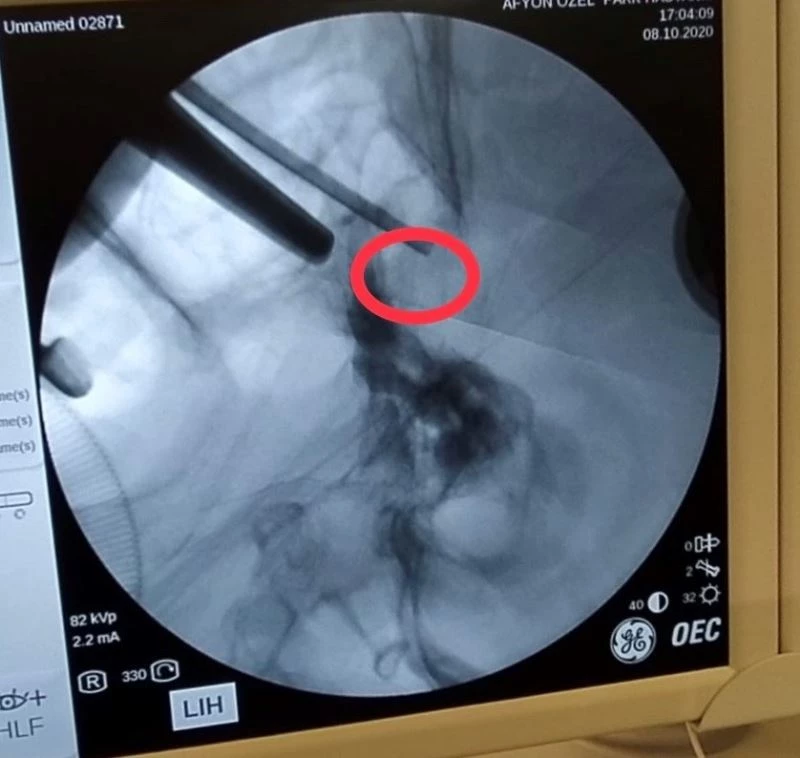

Afyonkarahisar’da özel bir hastanede gerçekleştirilen ameliyatta hastanın beyninde bulunan tümör burun deliklerinden girilerek başarılı bir operasyonla çıkarıldı.

Görme kaybıyla kentteki özel bir hastaneye başvuran ve ismi açıklanmayan Uşaklı 72 yaşındaki hastaya yapılan tahlil ve tetkikler sonucunda hipofiz bezine yerleşmiş ve kafa tabanındaki sinirlere bası yapan bir tümörün varlığı tespit edildi. Beyin ve Sinir Cerrahi Uzmanı Op. Dr. Celal Özbek Çakır tarafından operasyon yapılmasına karar verildi. Ameliyata alınan hastanın burun deliklerinden girilerek beynindeki tümör alındı.

Operasyon sonrası açıklamalarda bulunan Çakır, transsfenoidal cerrahinin burun boşluğundan girilip hipofiz tabanına ve oradan hipofize ulaşılıp yapılan cerrahi olduğunu söyledi. Çakır, "Hastamız da 72 yaşında, ani gelişen göz kapağında düşme, görme kaybı ve şiddetli baş ağrısı ile bize geldi. Hastanın tetkiklerinde sella dediğimiz kafa tabanında hipofiz bezinin yerleştiği boşlukta büyük bir kitle ve buna bağlı bu bölgedeki kranial sinirlerin bası altında kaldığını görerek cerrahi kararı aldık. Hastaya transsfenoidal girişimle tümörü tamamen boşalttık ve problemsiz olarak servise aldık" dedi.